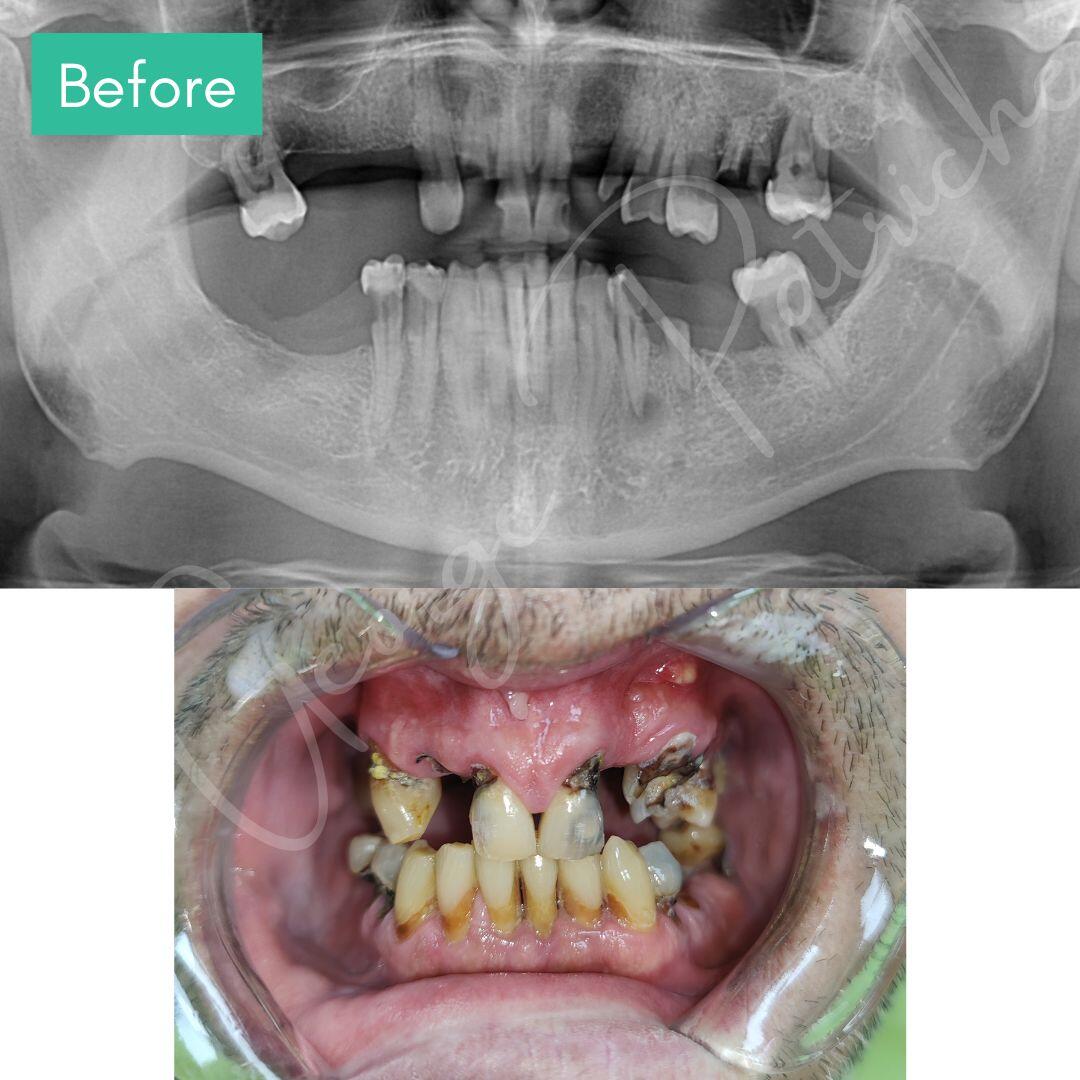

Before & After